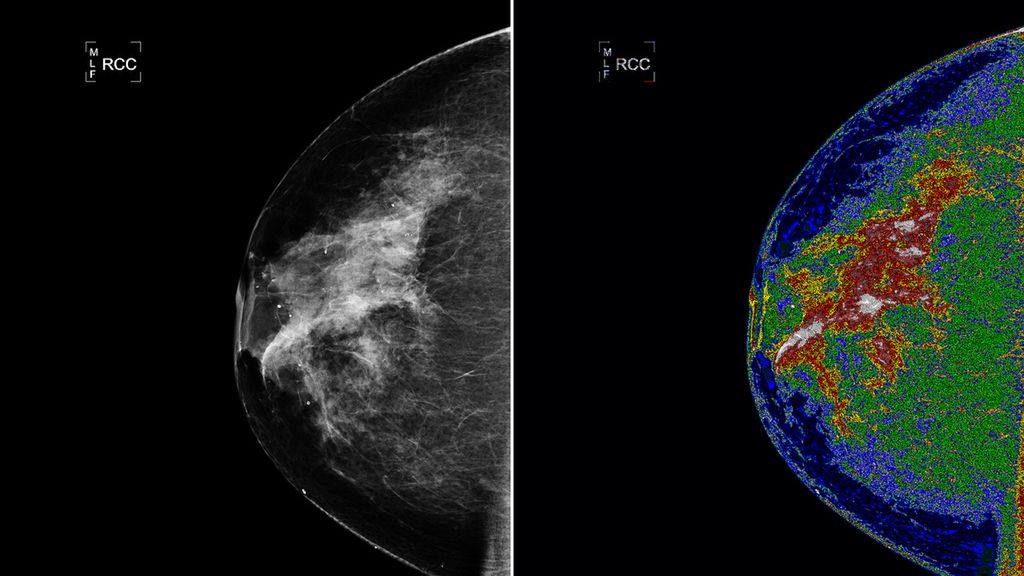

Goddard Space Flight Center w Greenbelt wspólnie z małą firmą zajmującą się tworzeniem oprogramowania medycznego - Bartron Medical Imaging, Inc. (Connecticut) - opracowały system medyczny MED-SEG. Dzięki temu lekarze otrzymają lepsze wyniki z aparatów rentgenowskich, ultrasonografów i mammografów. Pokazuje to najlepiej zdjęcie powyżej - po lewej widzimy zwykłe zdjęcie, po prawej - zdjęcie z użyciem nowego systemu. Jak powiedział dr Thomas Rutherford, dyrektor Wydziału Ginekologii Onkologicznej na Yale University: